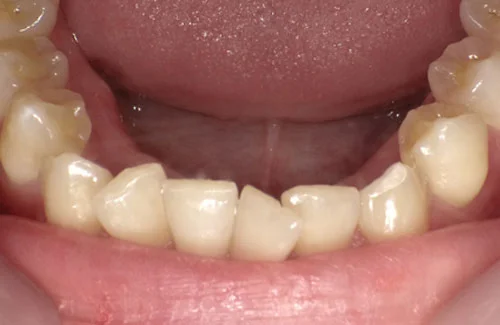

<症例7>歯がガタガタで噛み合わせが悪くお悩み

抜歯無し・マウスピースのみで矯正した症例です。

もともと歯列弓が非常に狭く、V字に近い形をしていたので噛み合わせも非常に不安定でした。

また、下顎前歯部がかなり上の方に生えていたため、下の前歯が上の前歯を突き上げてしまい出っ歯の状態になっていました。

現在では見た目はもちろん、臼歯の噛み合わせも改善しております。

患者様と症状

主訴:歯のガタガタ、噛み合わせが悪い

性別・年齢:20代女性

問題点:叢生(重度)、V字歯列弓、ディープバイト

診断:前歯部の叢生を伴うアングルⅠ級、骨格性Ⅰ級の不正咬合

主なリスク:臼歯の移動に伴い一時的に咬合しにくくなる、歯肉退縮

症状:叢生(そうせい) 過蓋咬合(かがいこうごう)

治療内容

治療期間:1年10ヶ月

治療費用:990,000円(税込)

プラン:Full2プラン

抜歯:無し

再診治療費:無し

追加治療費:無し

保定装置費:無し

治療前後の写真